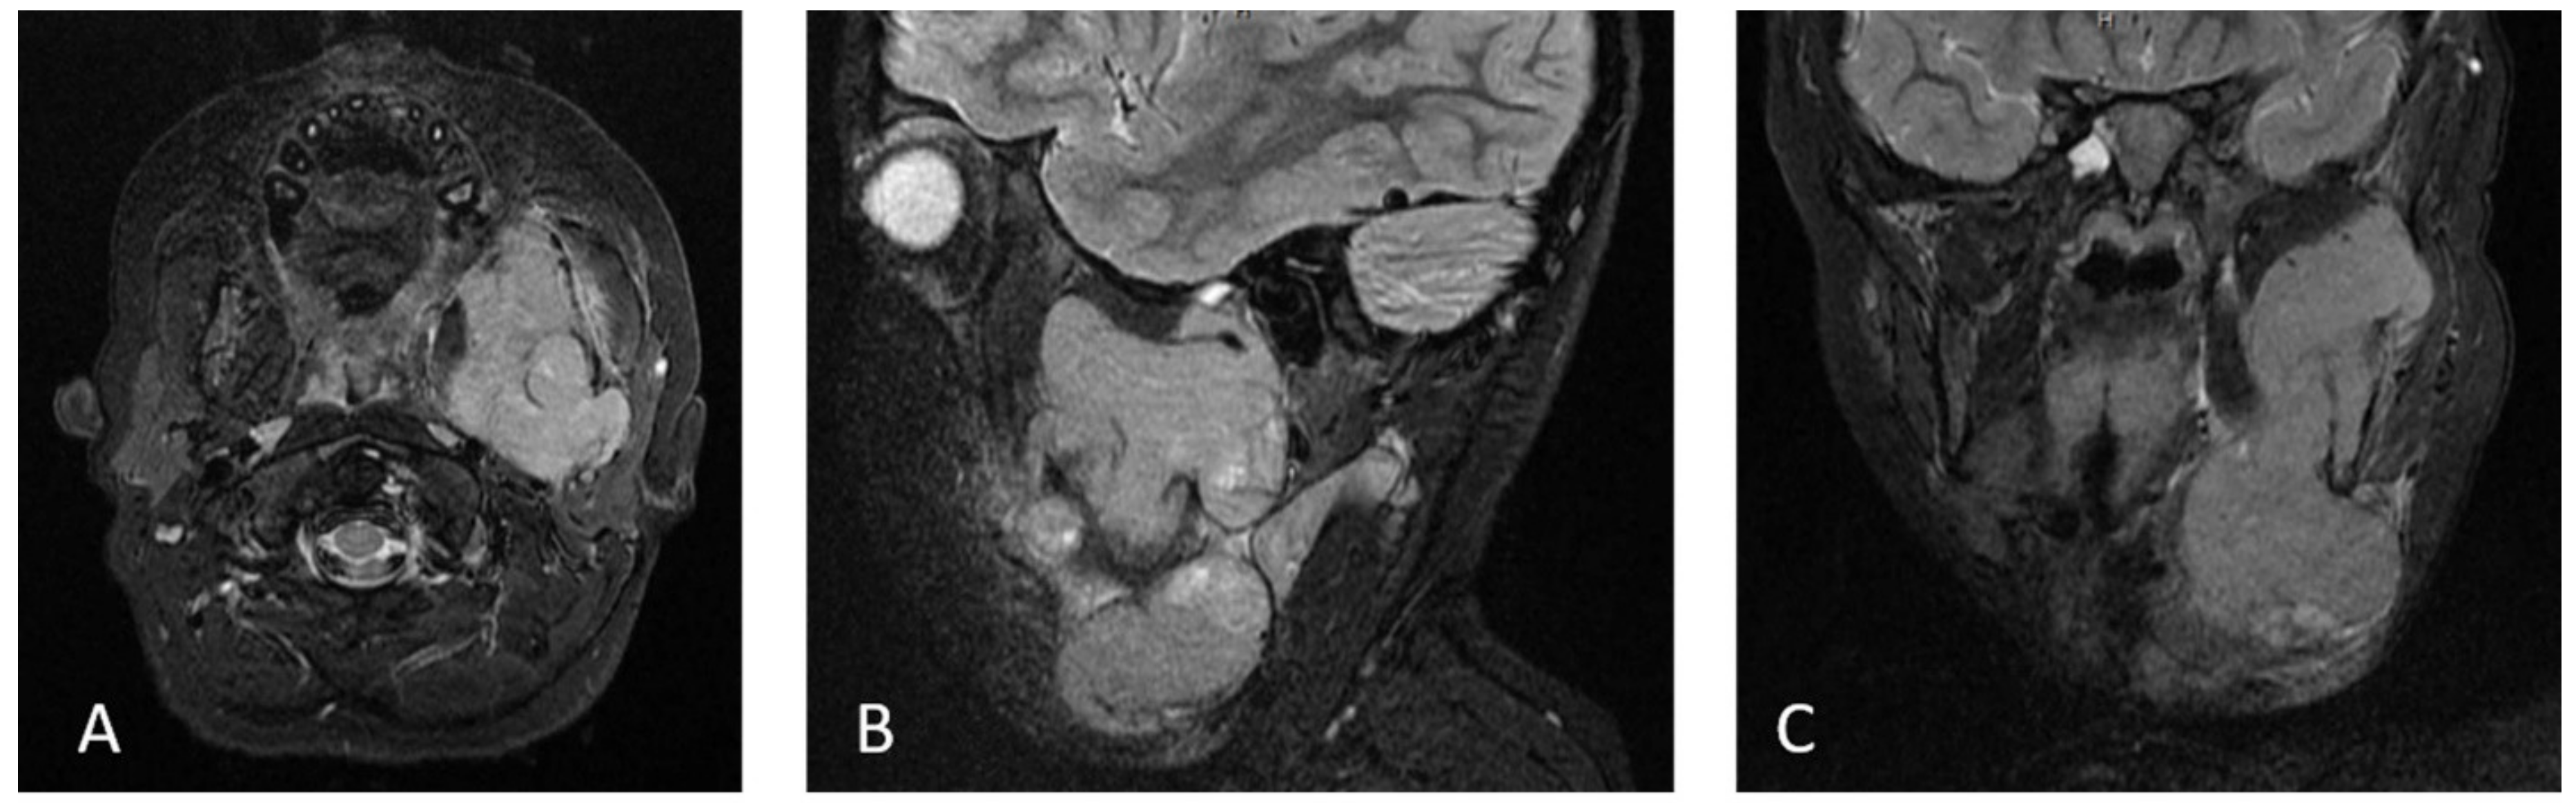

2. Case Report